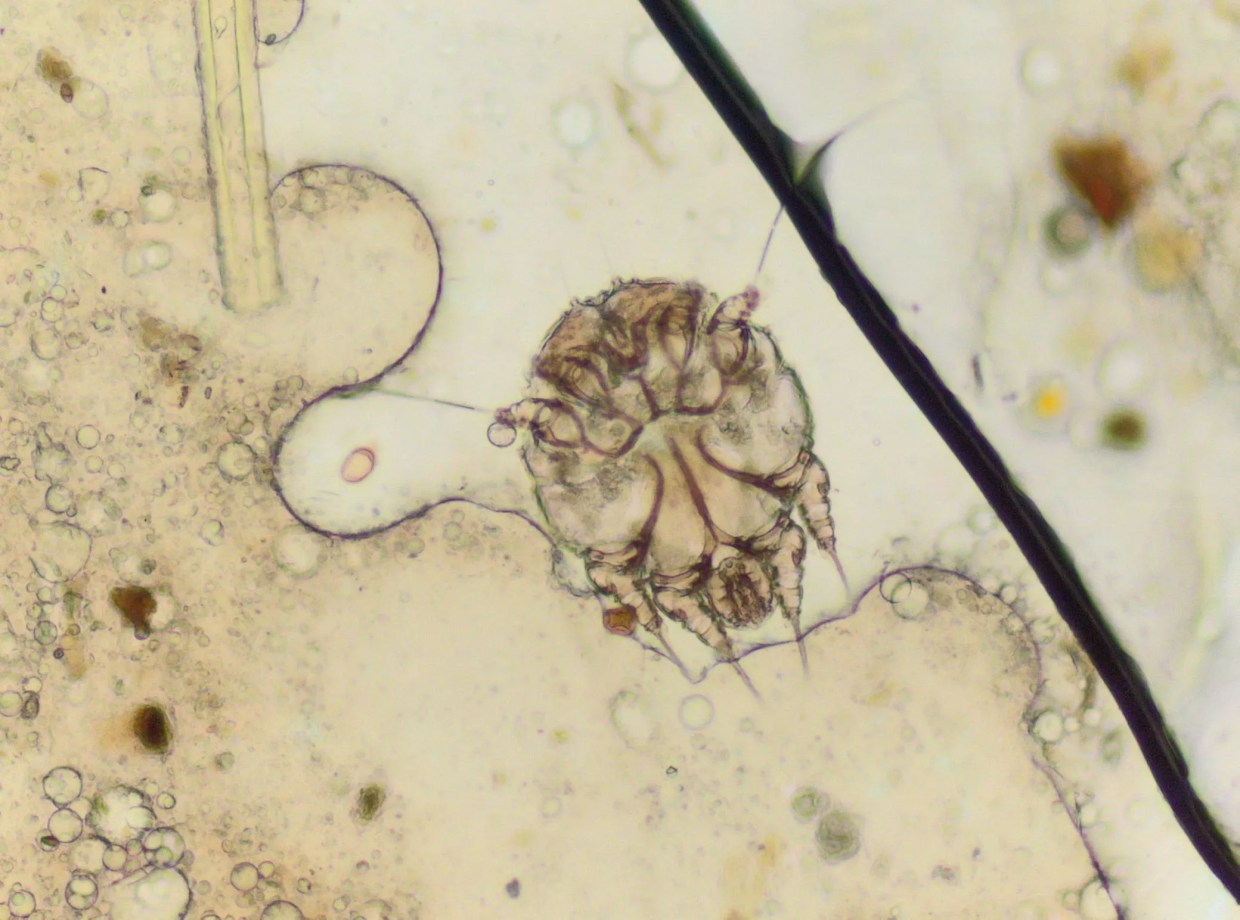

Scabies Outbreak at Immigrant Detention Facility in Aurora

By Conor McCormick-CavanaghDecember 10, 2019

Six detainees have scabies at the immigrant detention facility in Aurora.